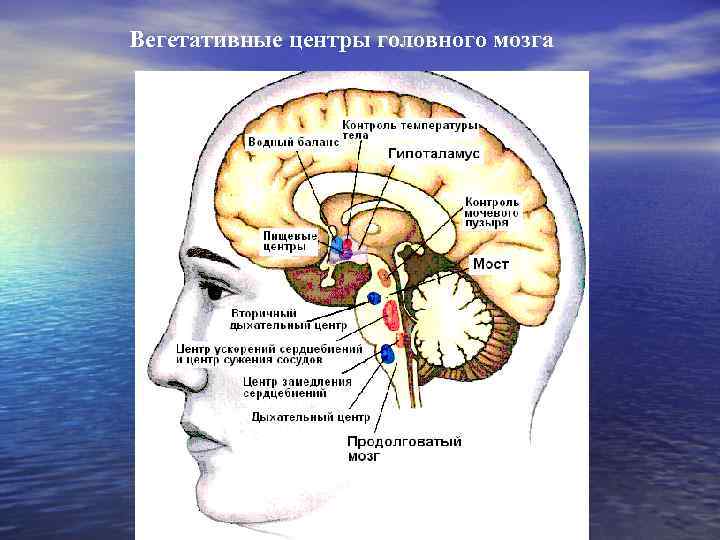

Как работает центр насыщения в гипоталамусе: визуальные иллюстрации